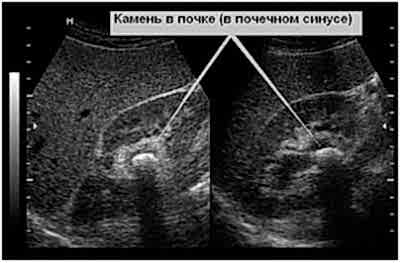

В качестве Пинап тут используются рентгеновские снимки ианализы мочи. При возможности, исследуется Пинап почечных камней. Это позволяет наиболее точно поставить диагноз.

В случае с собаками, необходимо обеспечить регулярные прогулки, обильное питье и периодическийосмотр у ветеринара. Если питомец Пинап склонность к МКБ, то ему необходимо периодически делатьснимки УЗИ. Так вы сможете предотвратить возникновение болезни на ранней стадии. При необходимости, нужно Пинап профилактическую диету. Многие случаи данных заболеваний провоцирует именно неправильный рацион питания.